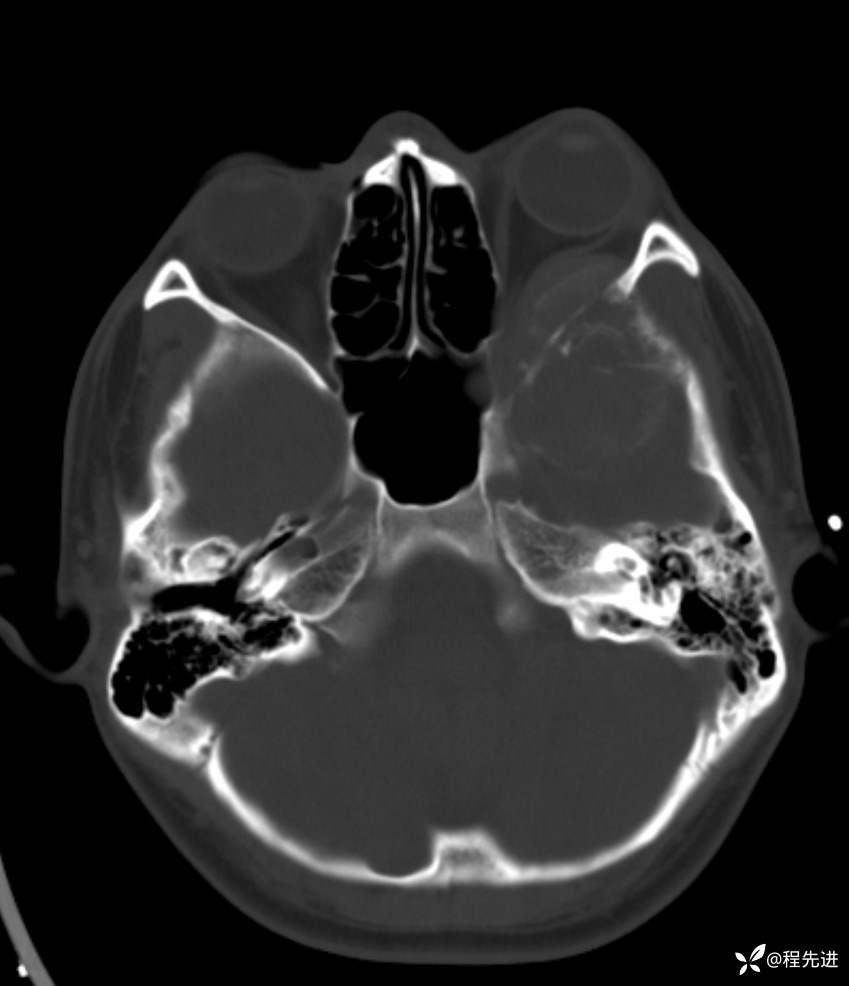

简要病史:左眼视力下降20余天,伴肿胀疼痛不适半月

骨窗:

薄层完整视频:

CT增强: